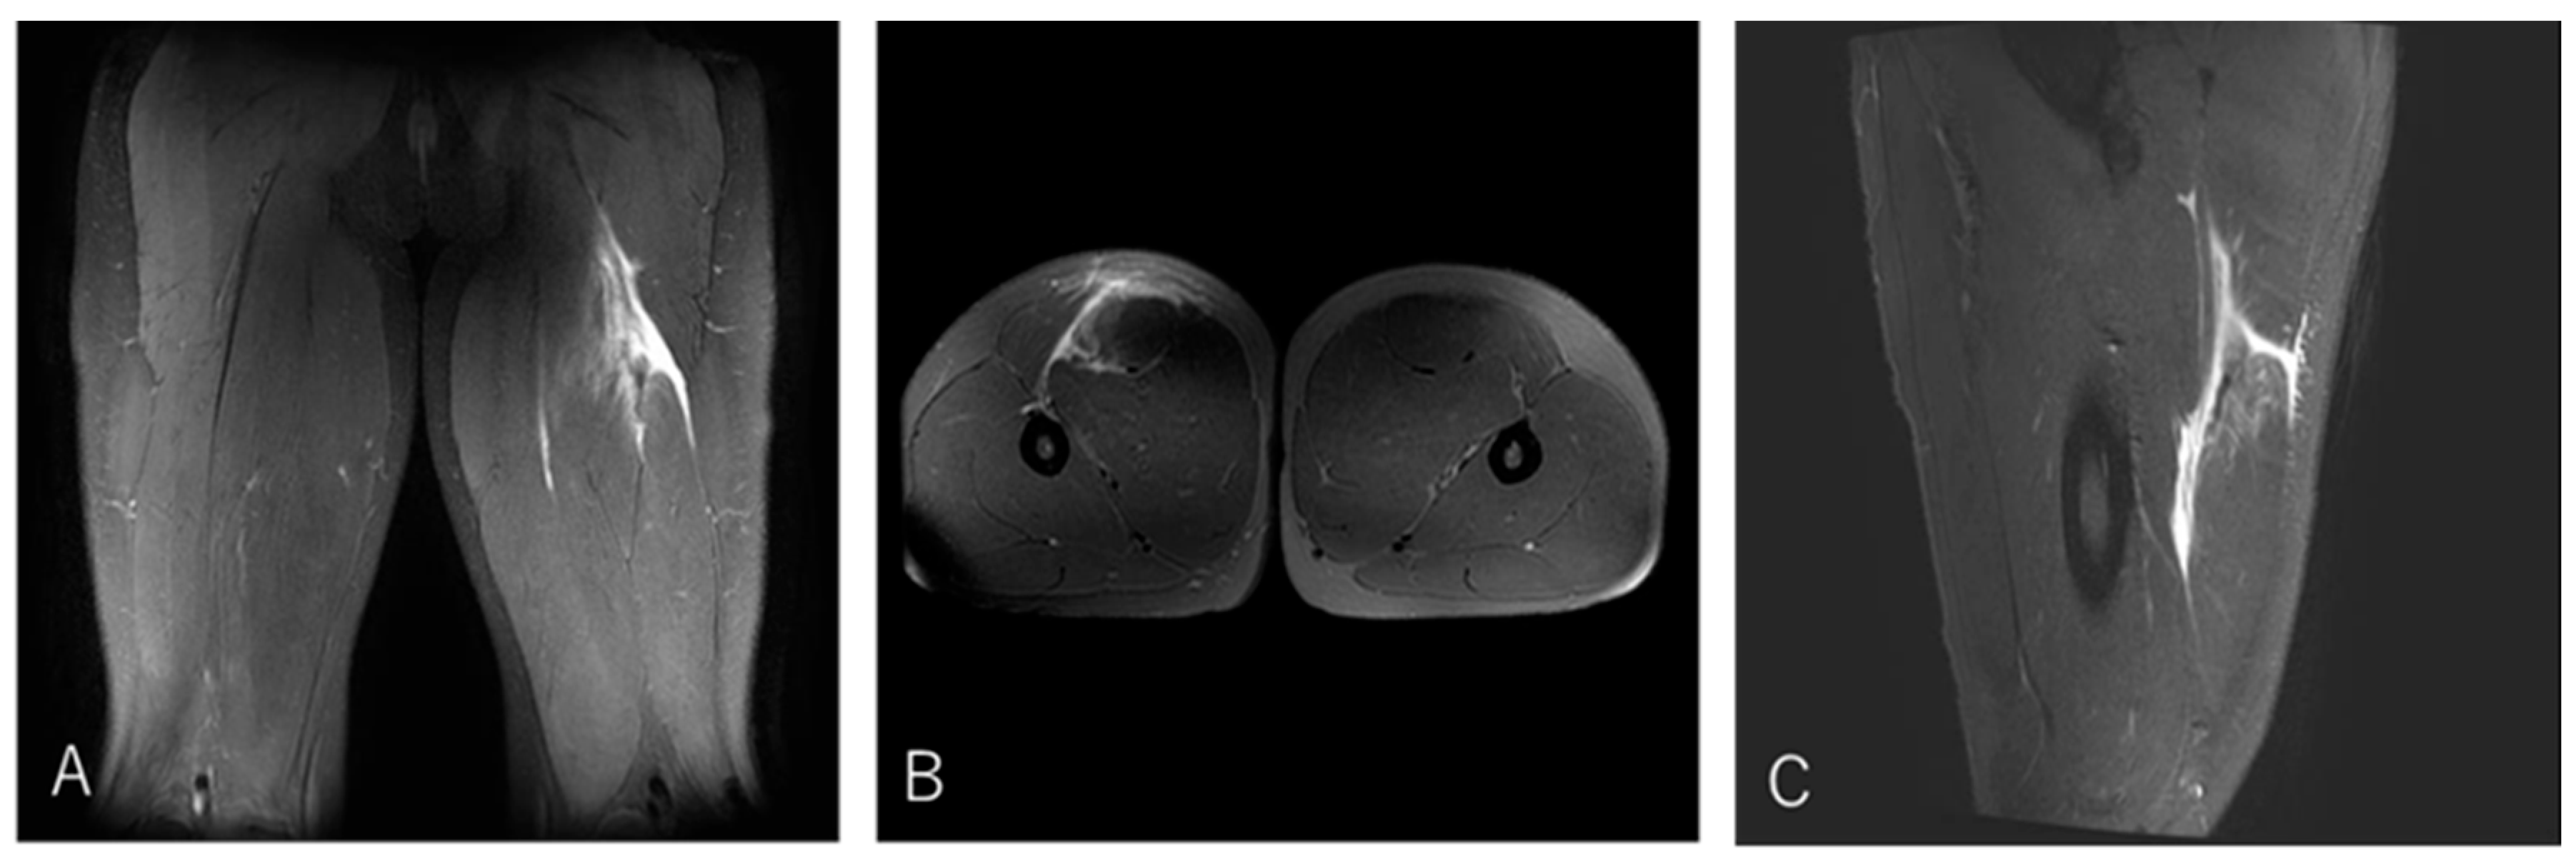

3.4.3. Case 3—Type I/Zone C (MTJ Injury), Grade 2

A 21-year-old scrum half (BK) developed pain in the proximal posterior thigh while changing direction to chase an opposing player. He returned to play after 10 weeks (Figure 6).

Figure 6. Case 3 MRI images: Conjoint tendon MTJ injury, Type I. (A) (Coronal image): The injured area was the proximal MTJ on CT, with haemorrhage observed bilaterally and tortuosity noted on CT. (B) (Axial image): prone position, bleeding is present on both BFLH and ST sides of the CT, and the CT is interrupted at the rupture site. (C) (Sagittal image): The CT is slightly retracted and accompanied by a haematoma.